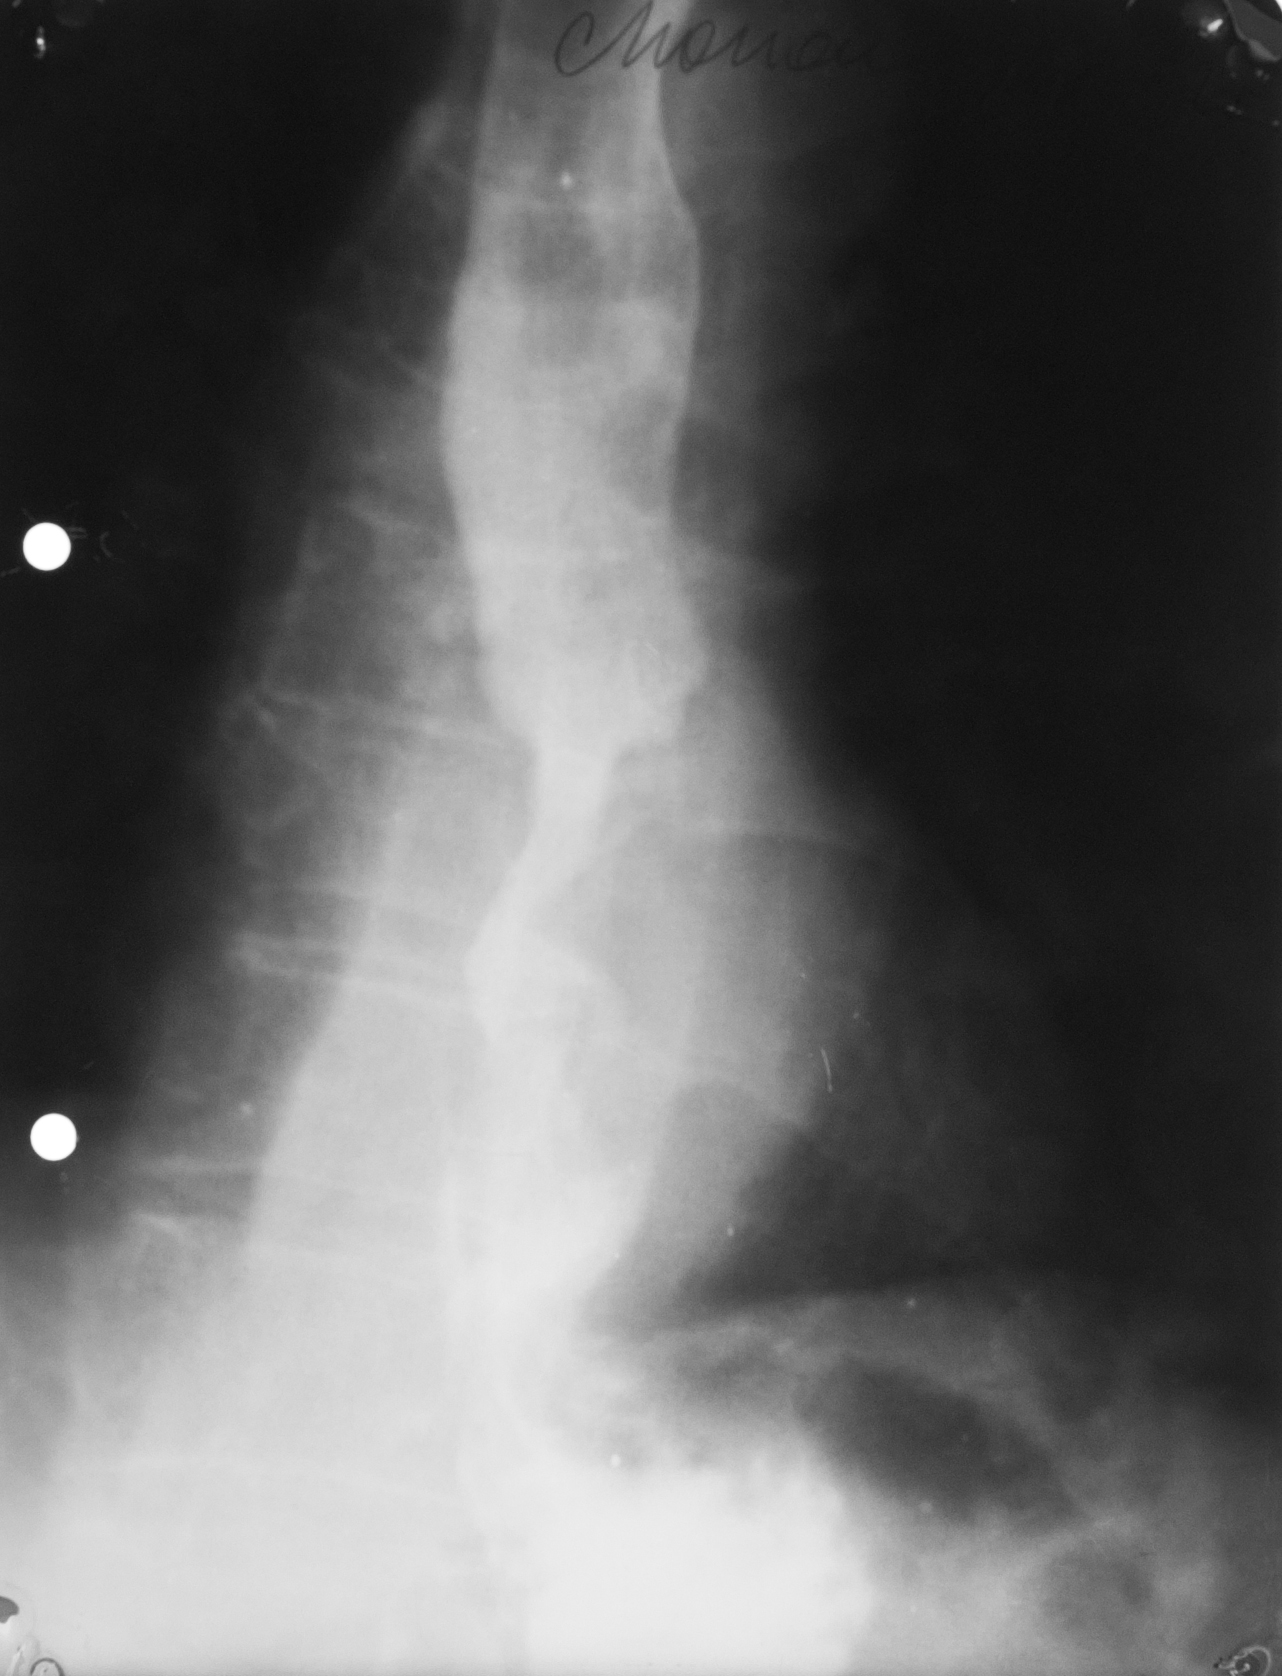

STENOZĂ DE TIP BENIGN

Tranzit baritat la nivelul esofagului

Se observă o stenozare pe distanță mare,axială,simetrică a esofagului=Stenoză de tip benign.Se observă și o mica ulcerație:imagine de adiție triunghiulară la nivelul extremității superioare

STENOZĂ DE TIP MALIGN

Stenoză excentrică cu contur neregulat,pe o distanță mai mică

STENOZĂ DE TIP MALIGN

Contur neregulat,anfractous cu retrodilatare

Stenoză excentrică,nu este axială